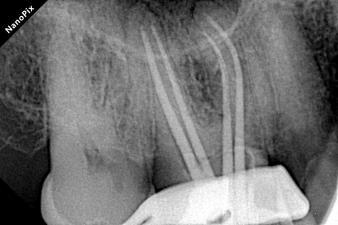

Confirming the dense, 3D fill of the entire root canal system.

Displaying the excellent final result, particularly highlighting the beautiful flow in the mesiobuccal root canals

In dealing with complex anatomies complicated by severe calcification and periapical lesions, the perfect combination of DENCO APEX-S (for precise WL control) and Only One File Blue (for superior flexibility even at large apical sizes)significantly enhances the safety, predictability, and success rate of complex endodontic treatments.